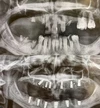

تسوس الأسنان

نقص الأسنان

ازدحام الأسنان

أمراض الأسنان واللثة

كيسات الفك